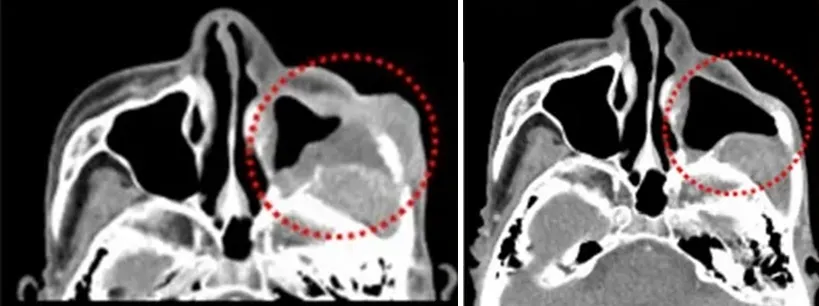

一位70多岁的男性,上颌窦癌术后放化疗复发,BNCT治疗1个月后,面颊和窦内的复发肿瘤几乎完全消失。